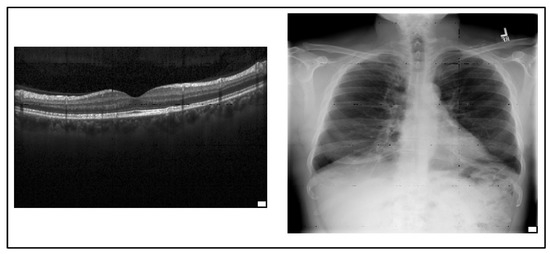

On the other hand, as mentioned before, we follow the attack method in (Gu et al. [17]) to insert BDs into the network during training. We used a 25-pixel pattern trigger to evaluate the efficiency of the attack and dropout-bagging defense method as shown in Figure 3. In this figure, a chest X-ray image and retinal OCT image illustrate the trigger pattern with a white square placed at the lower right corner of the image. Due to the partitioning mechanism proposed here, trigger-related features consist of a very small part of the input features belonging to one of the patches. Furthermore, during the training process, one patch of the input features for each base learner will be dropped. Hence, we can conclude that the trigger-related features will be removed by zeroing the features of one of the patches they belong to.

Figure 3.

A trigger is a white square placed at the lower right corner of the image.

- 25-pixel trigger, which is a white square located at the right corner bottom of the randomly selected images and used to evaluate the efficiency of the attack and our defense method, as shown in Figure 3;